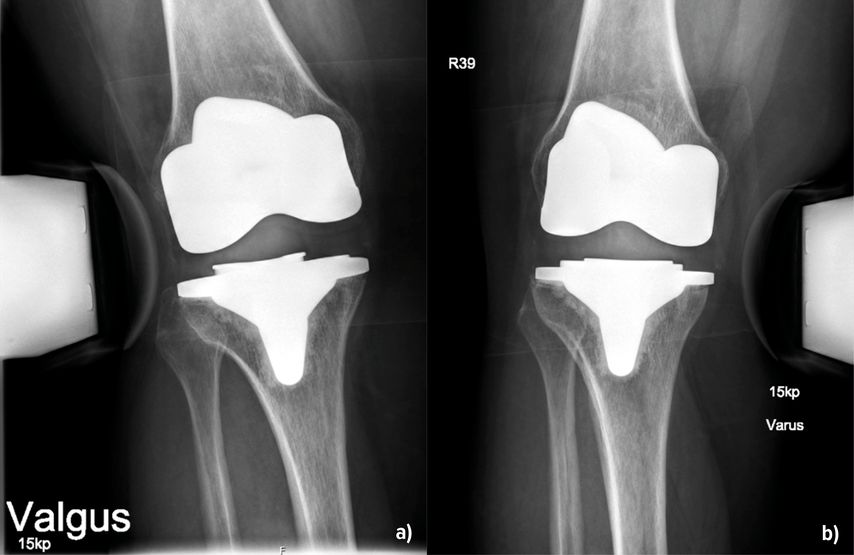

Die Instabilität von Knietotalendoprothesen beeinflusst die Zufriedenheit der Patient:innen und führt häufig zu Revisionseingriffen. In einer grossen retrospektiven Studie mit Erfassung von fast 40000 Patient:innen aus den Jahren 1996–2021 konnten Ergin et al. (2025) Risikofaktoren, welche mit einer Instabilität nach Endoprothetik einhergehen, darstellen. Dazu gehörten ein jüngeres Alter, das weibliche Geschlecht, ein Schlaganfall, tiefe Beinvenenthrombosen, Nickelallergie, Osteoporose und – überraschend – die Sklerodermie. Die Adipositas stellt demnach kein erhöhtes Risiko dar. Über die Details der Ursachen berichtet die Arbeit allerdings nicht, sondern beschreibt diese als multifaktoriell. Jedoch können die Autoren aus der eigenen klinischen Praxis berichten, dass durchaus Unterschiede in Bezug auf das Inlay bestehen. Entweder war dieses primär zu flach oder es ist zu einer Lockerung der Bänder im Verlauf gekommen. Auch der Verschleiss des Inlays über die Zeit spielt erfahrungsgemäss eine Rolle (Abb. 1). Bei der Differenzierung, welches Ausmass einer Varus- oder Valguslaxizität zu einem annehmbaren oder schlechten klinischen Ergebnis führt, fanden Mitsu-Uchi et al. (2025), dass eine mittlere Instabilität von 3–6mm im medialen Kompartiment für ein besseres postoperatives Ergebnis von Bedeutung sei. Eine straffe Implantation mit einer Instabilität von <3mm sowie Instabilitäten von >6mm führten demnach zu niedrigeren Zufriedenheitswerten bzw. Knee-Scores. Somit soll eine mittlere mediale Laxizität für ein besseres postoperatives Ergebnis sorgen, was bereits bei der Implantation Beachtung finden kann. Neben dem klinischen Nachweis ist die gehaltene Röntgenaufnahme geeignet, um den Befund zu verifizieren und zu dokumentieren (Abb.2). Bezüglich der Ursachen für Fehlschläge primärer Knietotalendoprothesen finden sich die Instabilitäten mit einer Häufigkeit von 7% bzw. 4,55% an 3. bzw. 4. Stelle. Vorwiegende Gründe für Revisionen sind hingegen periprothetische Infektionen (22,3% bzw. 47,73%), die aseptische Lockerung (20,5% bzw. 35,23%) und Bewegungseinschränkungen (5,68%) (Datta et al. 2025, Mozella et al. 2024). In einer Arbeit von Poilvache et al. (2025) wurde das Übergewicht als Risikofaktor für Komplikationen nach K-TEP untersucht. Die Hauptursachen für die initiale Revision waren die aseptische Lockerung mit 37%, die Instabilität (29%) und der Abrieb oder Osteolysen (13%). Die Arbeit erbrachte ganz klar, dass ein BMI >40kg/m2 tendenziell mit einer Reoperation korrelierte. Allerdings nicht wegen Instabilität, sondern wegen periprothetischer Infektionen, und das auch nicht signifikant. Der BMI als Ursache einer Instabilität nach Revision wurde hier ausgeschlossen. Brown et al. (2025) beschrieben ein erhöhtes Risiko mit Hinblick auf eine Revision als Folge einer Instabilität oder einer Lockerung bei Fällen, in denen die Femurkomponente grösser als die Tibiakomponente war. Die Autoren empfahlen, primär die Wahl der Prothesengrössen zu beachten, um Instabilitäten vorzubeugen. Auf die Infektionsraten und den anterioren Knieschmerz fand sich in dieser Kohorte kein Einfluss.

Abb. 2: 53-jährige Patientin 14 Monate nach KTEP-Implantation mit klinisch und radiologisch (a und b) nachweisbarer Instabilität – medial stärker als lateral